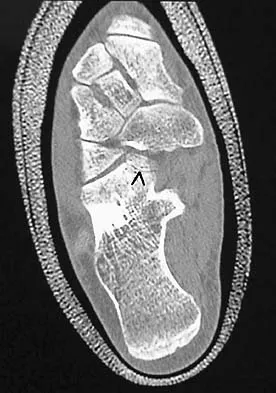

Question 11

Figure 11 shows the radiograph of an otherwise healthy 22-year-old man who sustained a midfoot injury in a motor vehicle accident 9 days ago. Treatment should consist of

Explanation